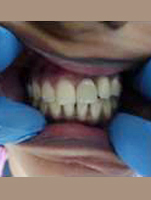

Placement of Bone Grafting

Post Operation

Use of Bone Graft & GTR membrane for an Implant

After Placement of Prosthesis